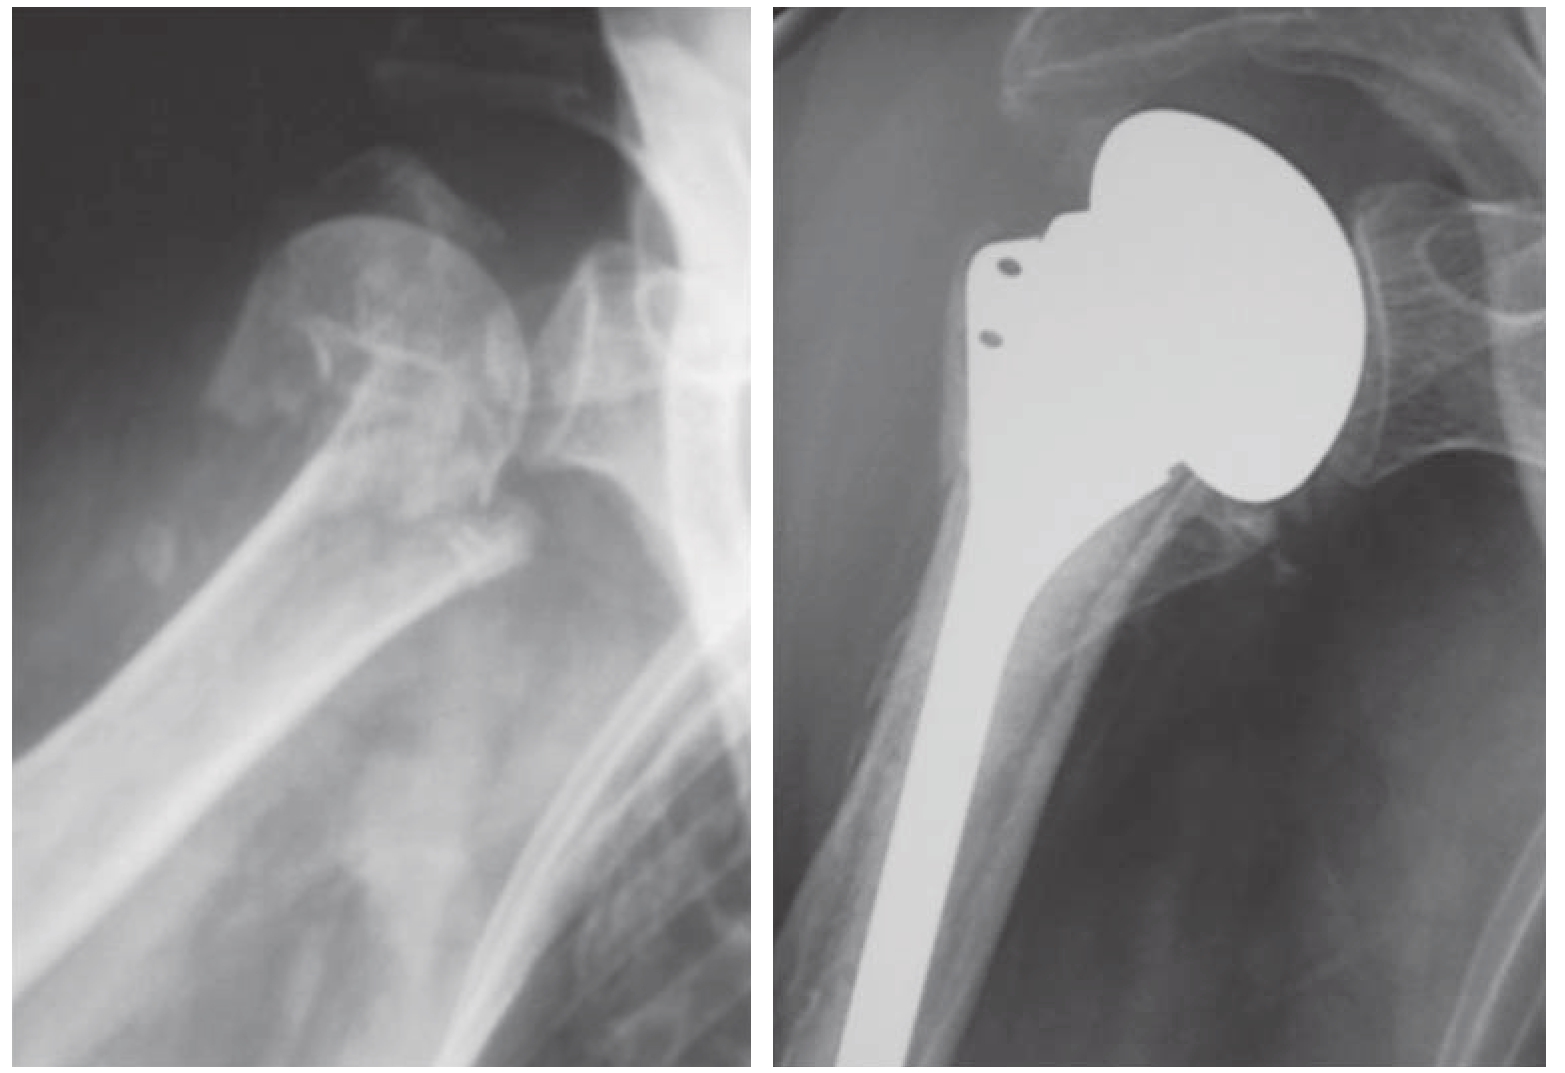

髓内钉主要适用于移位的肱骨外科颈两部分骨折,尤其是骨折线延伸到肱骨干的骨折,以及病理性骨折[19,20]。但其对肱骨近端骨结构的完整性和骨质量要求较高,使其在骨质疏松骨折中应用受限[21]。值得注意的是,随着髓内钉设计的发展,其使用适应证也在发生变化。目前肱骨近端髓内钉已发展到第三代,其主要特点是近端螺钉的锁定设计、多平面多角度的“多维”螺钉固定、内侧距支撑螺钉等,可实现交锁螺钉与主钉的锁定,从而达到角度稳定固定;“钉中钉”的设计可把持近端内后侧骨质最好的部位;多个方向锁定螺钉可以固定大、小结节骨折块;锁定螺钉尾部的缝线孔可以进行肩袖的固定等,大大提高了髓内钉对骨质疏松骨的固定稳定性[10,22]。因此,髓内钉也被用于三部分骨折甚至部分四部分骨折(图3—4),但目前并不推荐在四部分骨折应用髓内钉[23]

img

图3—4 第三代髓内钉治疗肱骨近端三部分骨折[22]